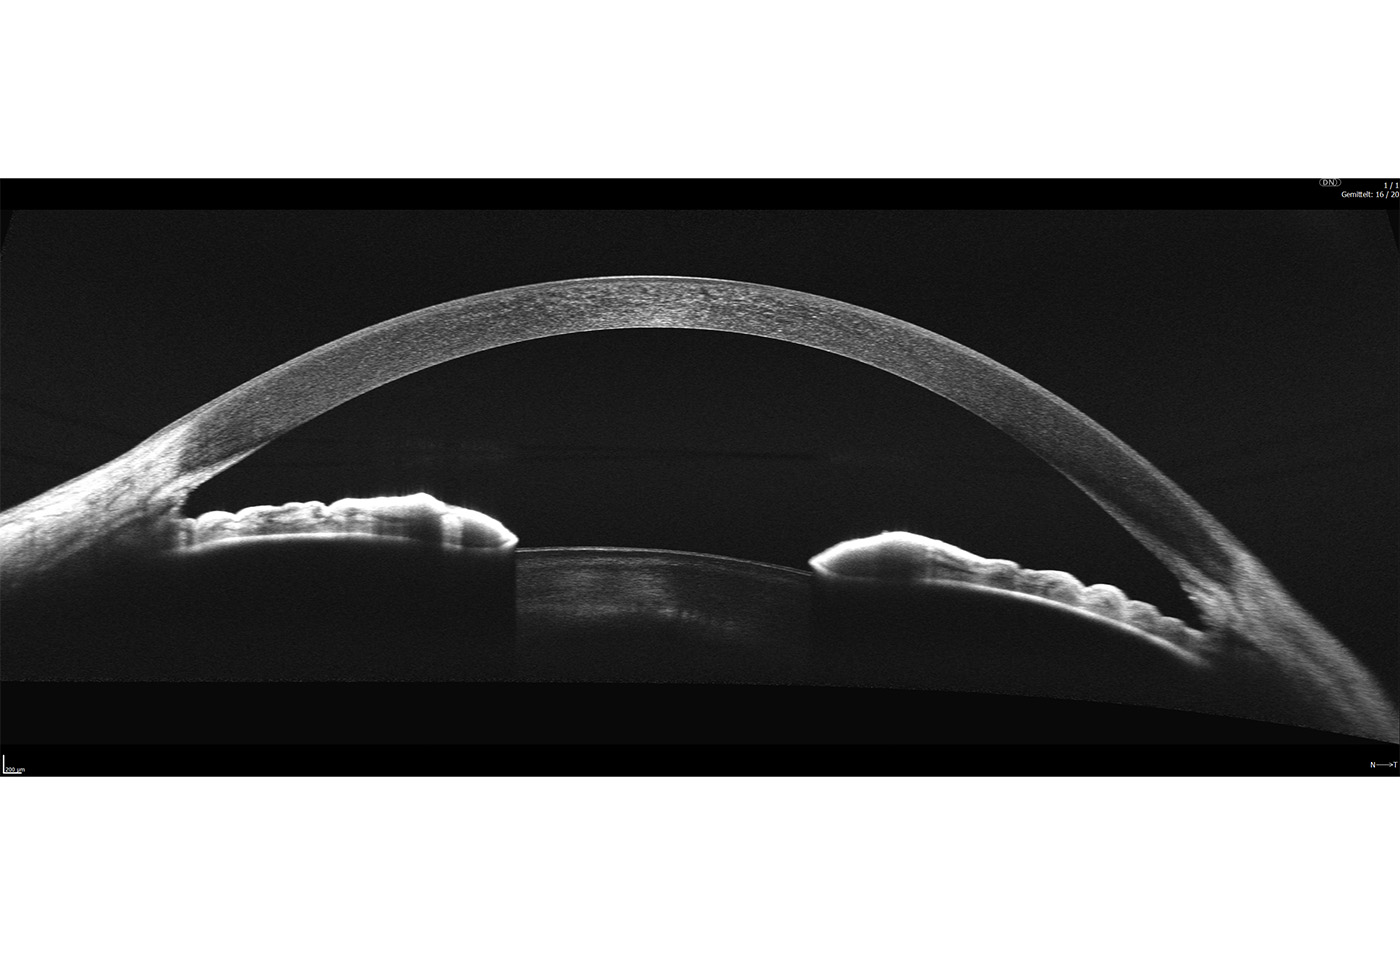

Full Range-Aufnahmen

Das Extended Depth Retina Imaging, welches auf der Full Range-Technologie basiert, bietet Scans mit größerer Tiefe für eine zuverlässige und bequeme Kontrolle von schwierigen Fällen. Dank der Scans mit großer Tiefe ist dieser neue Bildgebungsmodus perfekt für die Diagnose von sehr stark kurzsichtigen Patienten geeignet. Außerdem bietet sie einen Überblick über die gesamte Vorderkammer, von Hornhaut bis zur Augenlinse.

- Darstellung des vollständigen vorderen Systems

- Messung beider Kammerwinkel in einer Aufnahme

- Automatische Pachymetrie

- Analyse des Kammerwinkels

- Darstellung der Iris